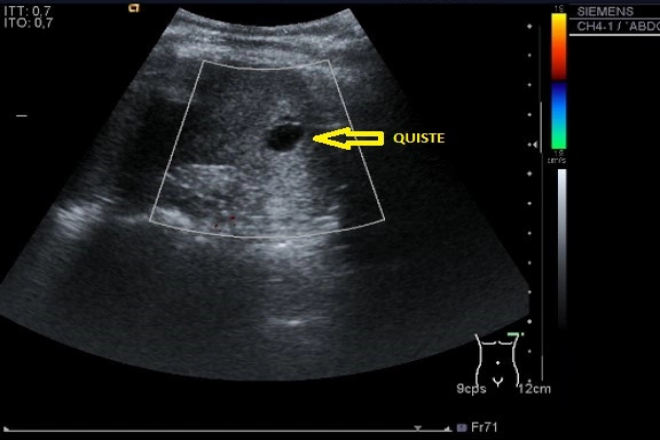

Mujer de 30 años, sin antecedentes de interés, que se realiza un USG ginecológica de rutina es diagnosticada de masa pélvica. Se completa estudio con una TAC, en donde se observa un bazo errante visualizando el pedículo vascular que desciende desde hipocondrio izquierdo.

Se realiza TAC abdominal con medio de contraste en el que se aprecia esplenomegalia con ausencia de captación del medio de contraste y una imagen en con disposición espiral a nivel del hilio esplénico, que hacen sospechar de una torsión esplénica.

El USG y TAC son medios no invasivos de gran utilidad que nos dan un diagnostico rápido ya que el primero nos informa sobre su grado de ecogenicidad del bazo y el segundo observamos alguna torsión o infarto, y permite demostrar una disposición de los vasos del hilio por medio del medio de contraste.